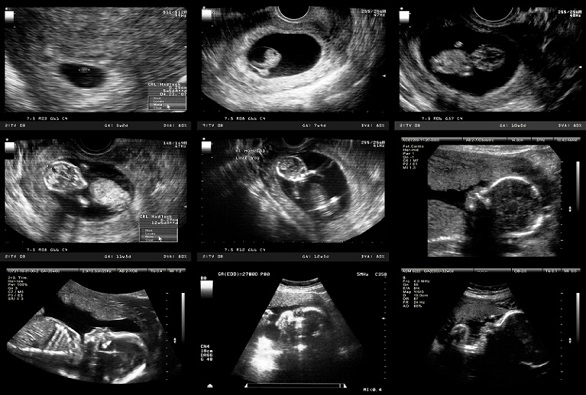

Sonography, or ultrasound, is a medical imaging technique that uses high-frequency sound waves to create real-time images of internal body structures, organs, and blood flow without using radiation. Performed by a diagnostic medical sonographer, the procedure involves applying a lubricating gel to the skin and moving a transducer over the area, which transmits sound waves and receives echoes to generate a picture on a monitor. It's a safe, non-invasive, and versatile diagnostic tool used for monitoring and managing various medical conditions, including pregnancy.